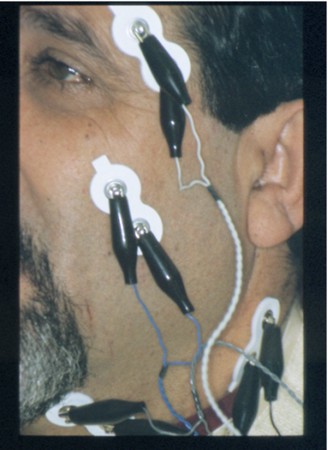

Bio Pack

Fig.6

Sensores Electromiográficos

Bio Pack

Fig.7

Receptor electromiográfico

Bio Pack

Fig.8

Magneto detector del

Movimiento

Bio Pack

Fig.9

Bobinas captoras del

Movimiento del magneto